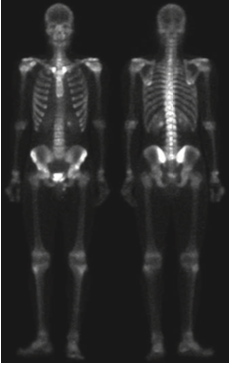

다른 방법은 어떤 방법이 있을 까요? 그 방법은 영상 그래디언트의 스무딩된 버전의 마스크를 사용하는 것입니다. 이러한 과정을 가능한 이유는 미분의 특성에 기인합니다. 라플라시안 필터는 애초에 2차 미분 연산입니다. 따라서 세세한 디테일 개선에는 좋은 결과를 얻을 수 있습니다. 하지만 노이즈가 많은 입력 영상을 받으면 출력 영상 역시 노이즈가 많게 됩니다. 하지만 로버츠나 소벨 연산과 같은 1차 미분 연산자는 라플라시안 필터에 비해서 노이즈나 미세한 디테일에 적은 반응을 보이고, 노이즈나 미세한 디테일을 얻는다고 해도 스무딩을 통해 제거 가능합니다. 따라서, 그래디언트 기반의 필터링을 통해서 엣지를 추출한 뒤 혹시나 남아있는 노이즈를 제거하기 위해 스무딩을 적용하는 것을 샤프닝된 영상의 입장에서는 골격의 마스크로 볼 수 있기 때문에 두 영상을 곱한 결과를 사용하는 것이 합리적입니다. 이를 위해서 위의 사진과 같이 입력 영상에 소벨 연산을 적용하게 됩니다.

다음으로 기울기 영상에 스무딩을 적용하여 약간의 노이즈를 제거해줍니다. 그러면 이를 마스크로 취급하고 샤프닝된 영상과 곱을 취해줍니다.

그 결과 영상 내의 강한 엣지들이 더 많이 남아있으며 노이즈는 라플라시안만 활용한 것에 비해서 더 줄어든것을 관찰할 수 있습니다. 이제 강한 엣지 영상을 샤프닝하는 데 사용해주면 됩니다.